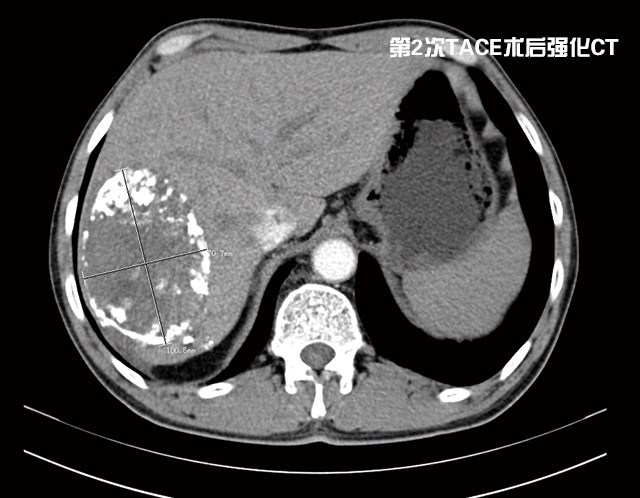

期間劉大爺共經(jīng)過(guò)了2次介入治療,一個(gè)月前他來(lái)普外科復(fù)查時(shí)醫(yī)生告訴他腫瘤已明顯縮小,可以手術(shù),劉大爺心里一陣高興。

經(jīng)過(guò)充分準(zhǔn)備后,由李森主任為他成功實(shí)施了肝第Ⅶ段、第Ⅵ段切除手術(shù),術(shù)后劉大爺恢復(fù)良好,精神抖擻,日前已康復(fù)出院。

據(jù)李森主任介紹,目前肝癌治療的首選方法是手術(shù)切除。如能早期發(fā)現(xiàn)并及時(shí)手術(shù),可提高遠(yuǎn)期存活率和生活質(zhì)量,甚至達(dá)到根治的效果。但很多肝癌患者發(fā)現(xiàn)時(shí),已是中晚期,因腫瘤巨大、伴肝硬化、肝功能差、肝內(nèi)轉(zhuǎn)移或多中心腫瘤存在等,而不能及時(shí)行手術(shù)治療,這種情況可以考慮先介入治療縮小癌瘤,待降期后再行手術(shù)切除,效果良好。目前肝巨大腫瘤的降期后手術(shù)切除為許多原來(lái)不宜手術(shù)切除的病人開辟了新路。